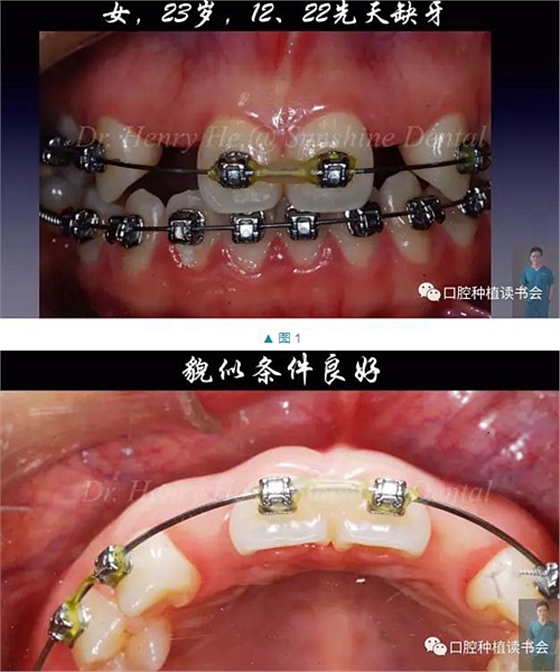

本臨床病例報(bào)告的患者為23歲的年輕女士,先天缺失12,22,為了給種植治療創(chuàng)造空間,2年前開始在外院正畸;正畸醫(yī)生認(rèn)為修復(fù)空間調(diào)整到位后,告知患者可行種植治療。

口內(nèi)檢查發(fā)現(xiàn):患者口腔衛(wèi)生良好,牙周健康,除了12,22缺失外,未見其它問題。12,22缺隙近遠(yuǎn)中大小約為8mm,臨床冠空間足夠(圖1,2)。患者中位笑線,中厚齦生物型,美觀要求很高(圖3)